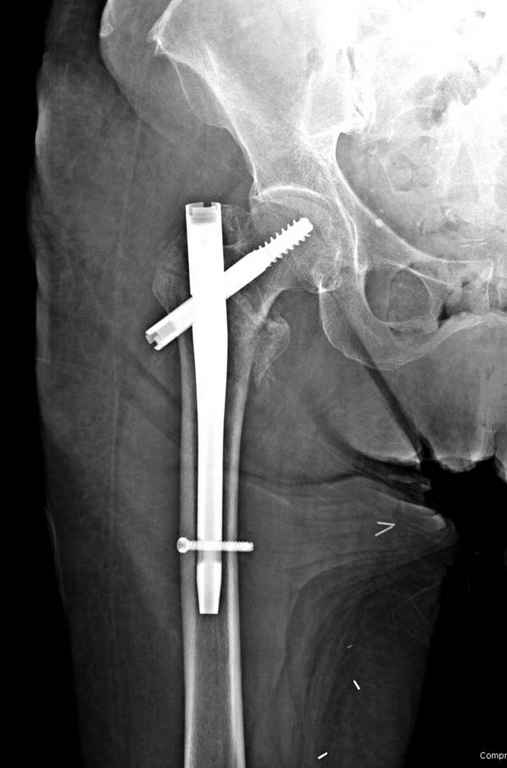

С приходом менее агрессивных блокируемых цефаломедуллярных гвоздей (Gamma 3 и другие) изменилась тактика лечения. Несмотря на то, что вся стабильность держится вокруг одного блокирующего винта, в большинстве случаев гвозди приводили к успеху.

В данном случае в головке бедра и в вертлужной впадине огромный дефект, навряд ли удалением импланта или заменой на другой можно сохранить сустав.

Вашему вниманию представляется похожий случай, пациентке 70, осложнился в течение одного месяца после операции. Ревизия с заменой сустава, кабельная фиксация на трохантер. При установке в дистальном диафизе обнаружен тонкий кортикальный слой и сделана профилактика от возможного перелома аллографтом.